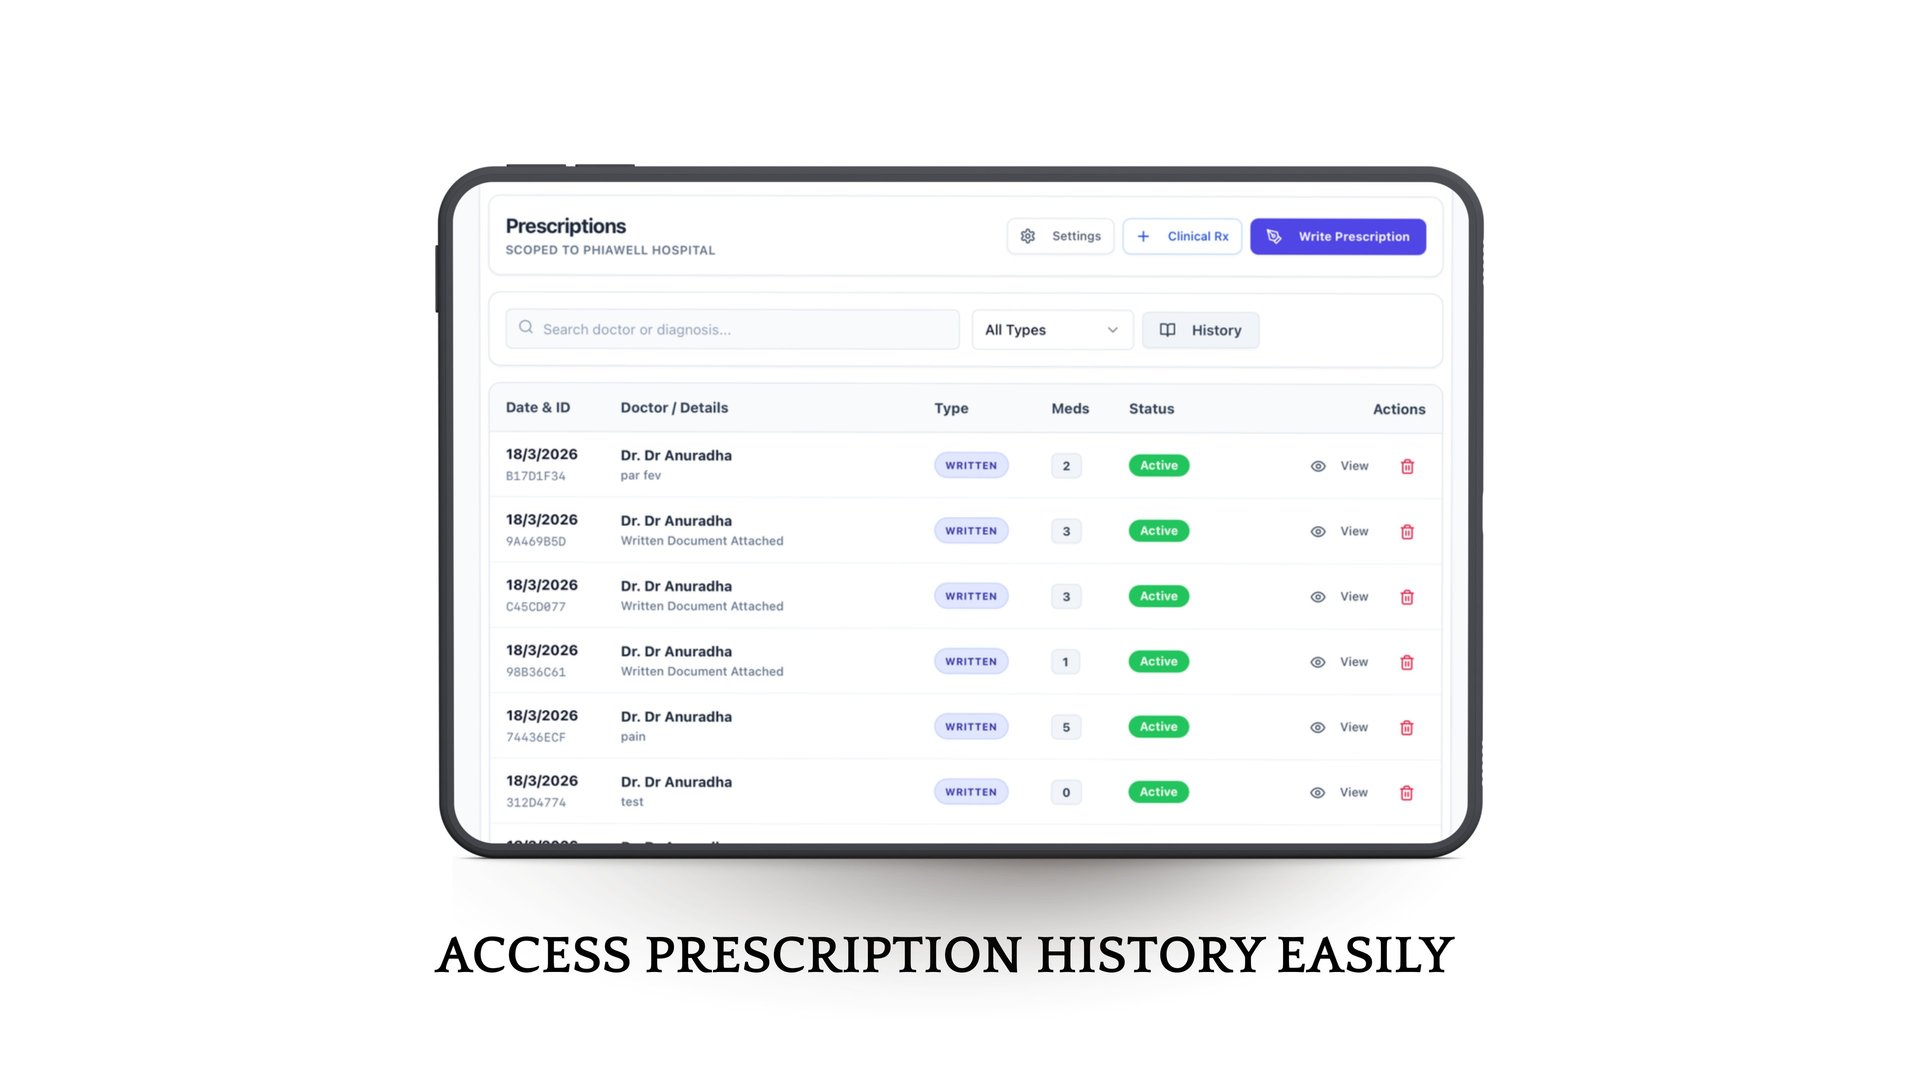

Time consuming prescription writing and managing past prescriptions.

AI assisted health summaries & prescription writing

Phia.Care brings all patient data—visits, prescriptions, reports, and history—into one seamless platform, reducing manual work and saving time.